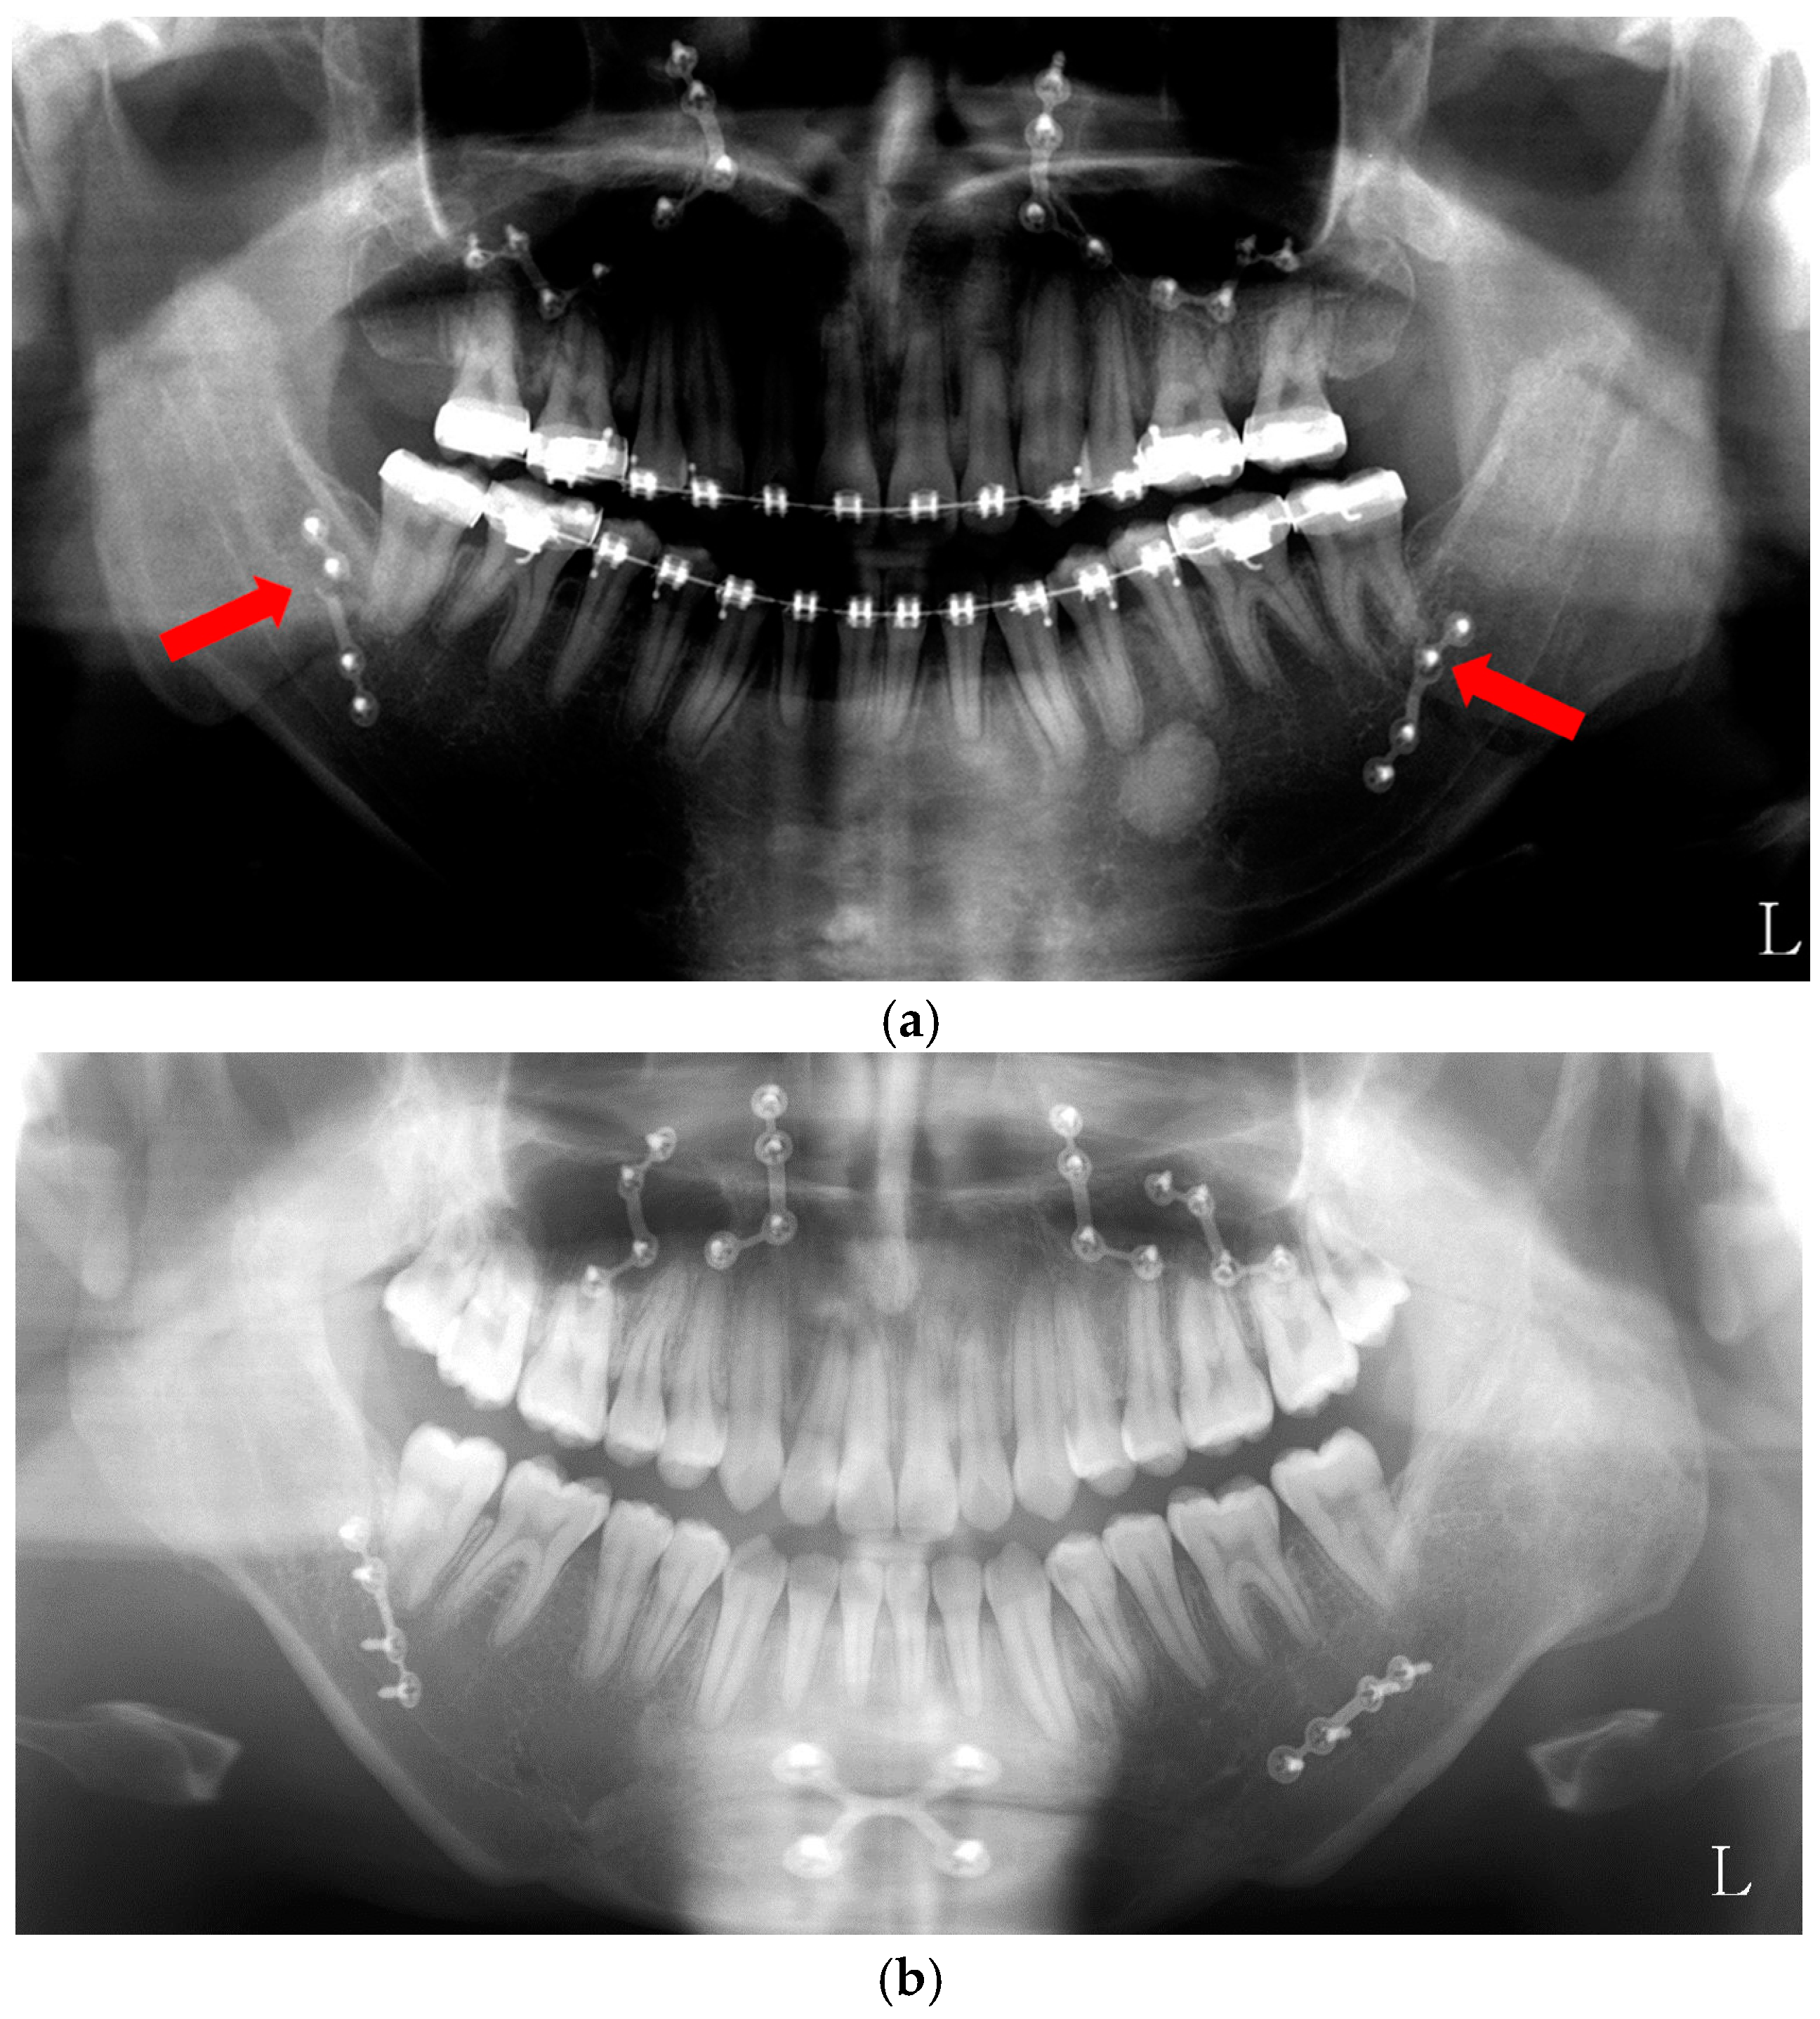

In the course of orthognathic surgery, patients usually prefer the intra-oral approach to the trans-buccal approach. However, compared to bi-cortical screws fixation, single plate fixation is less rigid fixation [82]. Patients who received bi-cortical screw fixation may open their mouth immediately after operation. In the case of single plate fixation, patients may be asked about intermaxillary fixation for three to four weeks. In our preliminary study [83], the patients (n = 7) received BTX-A injection into their masseter muscles along with two weeks of intermaxillary fixation. This group was compared to the patients (n = 11) who did not receive BTX treatment and the same period of intermaxillary fixation. The incidence of plate fractures was 14.3% in the BTX-injected group and 31.8% in the untreated control group (Figure 5). As the plate fracture is largely a fatigue type of fracture induced by the action of the masticatory muscles, reduced muscle power by BTX application may prevent the plate fracture. Though postoperative relapse has not been assessed, it may be reduced by BTX injection. To draw definite conclusions, further follow-up studies will be required.

Figure 5.

BTX treatment after orthognathic surgery. (a) Single plate fixation group after orthognathic surgery without BTX treatment (plate fracture in red arrow); (b) BTX injection group in both masseter muscles after orthognathic surgery.